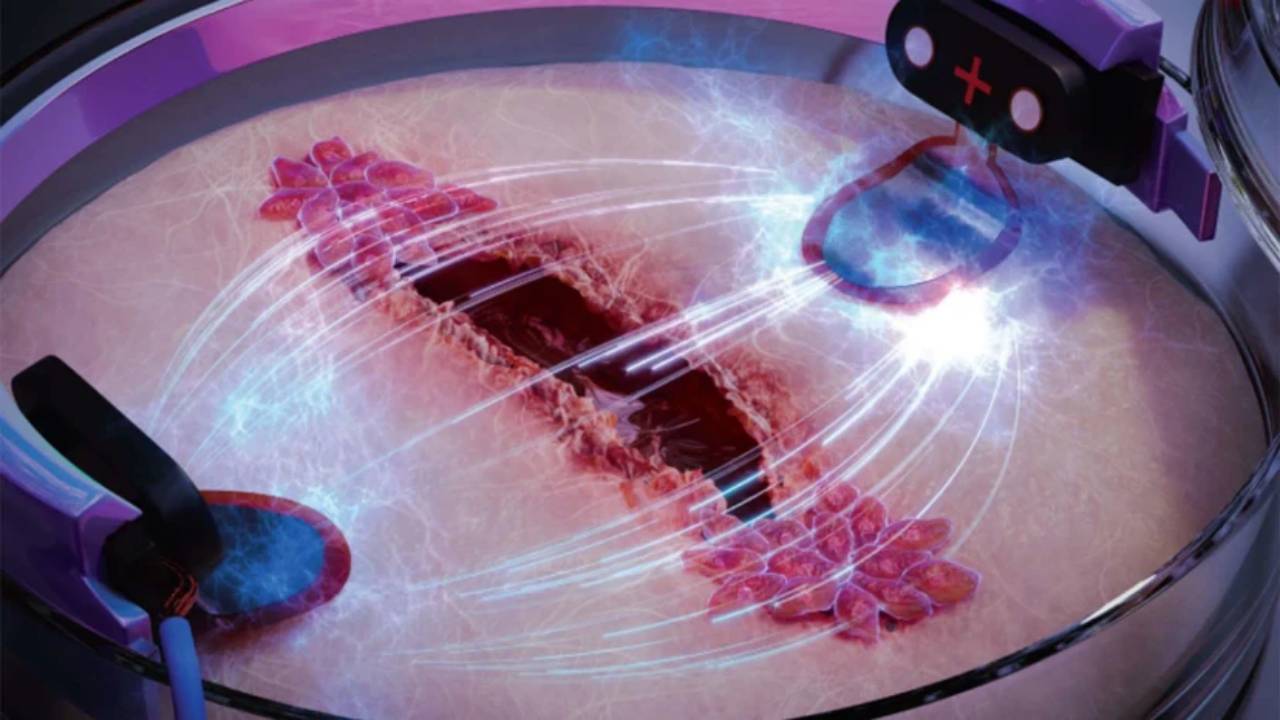

Identifican un nuevo tipo de célula en el corazón, relacionada con la regulación de la frecuencia cardiaca. Se espera que el ampliar su estudio sea clave para entender defectos y enfermedades cardiovasculares.

La célula tipo glial se encarga de dar soporte a células nerviosas que se encuentran en el cerebro y la médula espinal. Llamadas nexus glia se ubican en el tracto de salida del corazón, que es el lugar donde se originan varios defectos congénitos cardiacos.

Descubierta por primera vez en el pez cebra y luego luego confirmada en corazones de ratones y humanos. Los experimentos realizados en el pez mostraban que la frecuencia cardiaca aumentaba al extraer las células. Cuando se experimentó bloqueando el desarrollo glial con edición genética, los latidos se volvieron irregulares.

Para su descubrimiento emplearon técnicas científicas como imágenes de lapso de tiempo y secuenciación unicelular. Revelando la presencia de nexus glía en tejido de pez cebra, ratón y humano, en células que parecen apoyar la función y regulación del corazón.